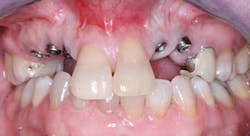

Observe Figs. 5-10 for a classic example of when crowns cannot be screwed onto abutments. The patient did not want to have bone grafting, and the implants were placed where there was minimally adequate bone. These implants were placed by a very competent periodontist. The significant angulation of the implants from the optimum angulation is easily observed with the impression copings on the implant bodies in Fig. 6. Custom abutments were mandatory, as shown in Fig. 6. The resultant crowns (Figs. 9-10) created a very acceptable esthetic result. It is very obvious that if crowns had been screwed onto the implants without an abutment, the screw entry would have been through the facial or incisal portion of the crowns.

FIG. 5 -- Implants placed in residual bone that was not at optimum angulation.

FIG. 6 -- Impression copings showing angulation of implants.